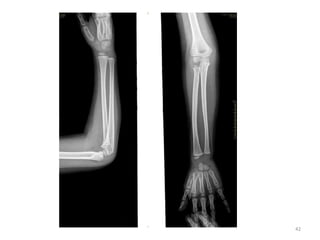

BONE OSSIFICATION CENTRE APPEARANCE CONJOINT EPIPHYSIS FUSION/UNION Humerus Capitulum Trochlea Lateralepicondyle Medial epicondyle 1 9-11 11-12 5-6 14-16 - 16-17 15-16 Radius Head Lower end 4-5 2 - 16-17 18-19 ulna Olecranon process Lower end 8-9 5-6 - 16-17 17-18 Carpal bones Capitate Hamate Triquetral Lunate Scaphoid, trapezoid Trapezium pisiform 2m of iul 3 m of iul 3 yrs 4 yrs 5 yrs 6 yrs 10-12 yrs - - 22

• 23.

• 24.